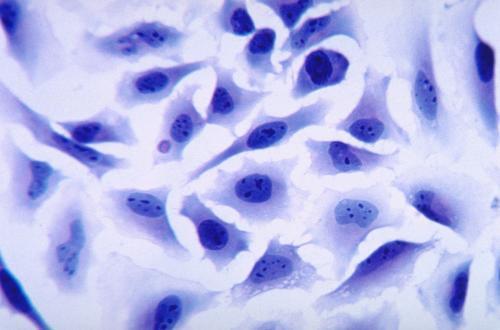

來源:藥渡撰文:四月的雨 編輯:丸子1概述許多藥物在體內往往具有溶解度低、保留時間短、生物利用度低以及靶向能力較差等限制,而且大分子藥物如核酸和蛋白質,還很容易被各種酶快速降解,從而失去活性。基于細胞的給藥策略因其獨特的生物學特性,如優良的生物相容性、低免疫原性、較長的循環時間以及跨越生物屏障的能力而備受關注。多種細胞可作為功能載體而用于藥物的遞送,如紅細胞、干細胞以及淋巴細胞等。由于這些細

轉自小藥說藥前言細胞因子,如白介素和干擾素,調節著生理學的各個方面,包括免疫、發育、生長和組織修復。鑒于細胞因子在健康和疾病中的核心作用,人們已經做了許多嘗試來利用細胞因子進行治療。然而,盡管人類基因組中編碼了許多細胞因子,但在臨床上成功應用細胞因子受體激動劑的例子依然很少。這在很大程度上是由于天然細胞因子的復雜生物學特性,通常會對多種細胞類型產生抵消作用。盡管這種多重作用對于確保體內平衡和調節細